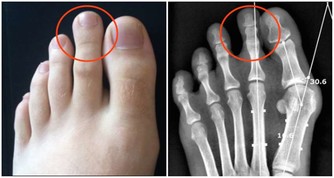

骨質疏鬆症的主要特徵是骨礦物質含量低下、骨強度降低、易發生骨折等。上了年紀的老人家走路駝背、身高降低,其實都是骨質疏鬆症的表現。

中老年人在做骨密度檢查時,若骨量減少9%以下為骨量正常,骨量減少9%~19%為骨量減少,骨量減少29%~39%則為骨質疏鬆、骨折危象。